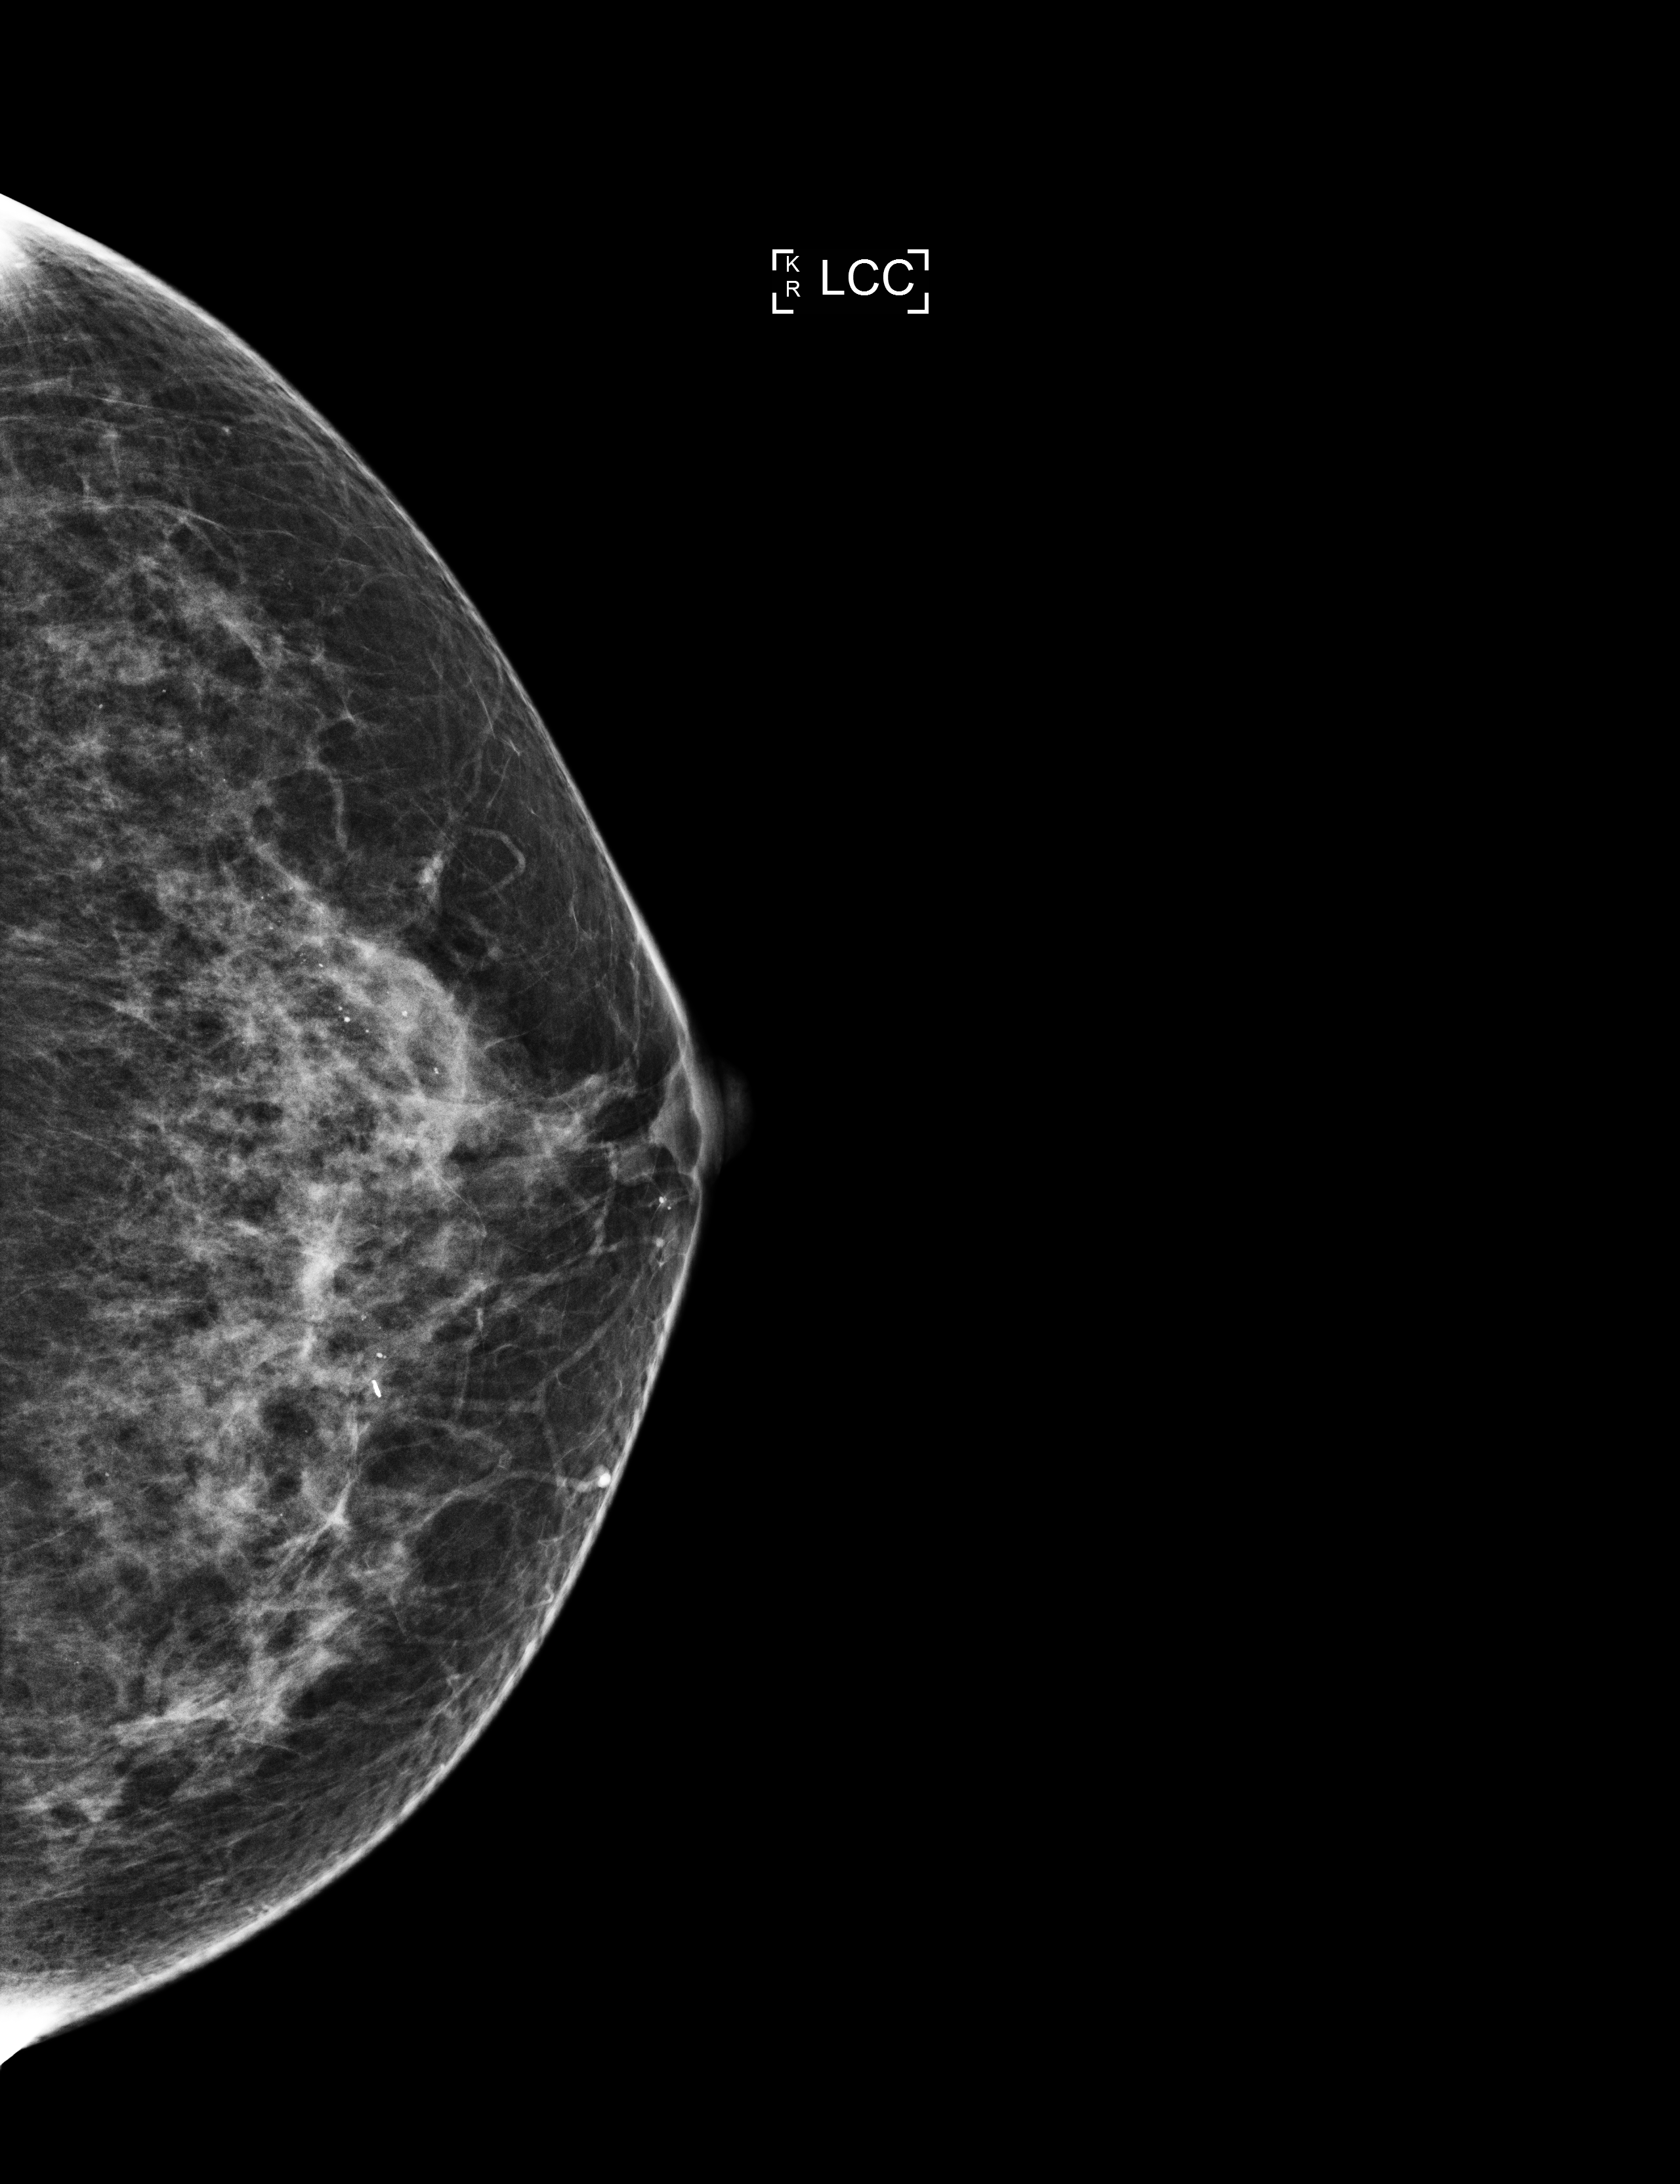

MedBot is a robot designed to help doctors to faster diagnose and interpret patients' imagistic investigations. This bot will take as input photos of a patient's x-rays and based on two CUSTOM deep learning models (one that deals with identifying breast tumors and one that identifies lung illnesses like pneumonia caused by COVID-19), will provide a diagnostic and automatically complete the patient's medical record. The patient's information needed for completing the medical record - first name, last name, birthdate, city etc is going to be retrieved using image preprocessing and OCR on the patient's ID.

We designed the machine learning model that detect the breast cancer or the lung diseases and we built the robot that interacts with it.